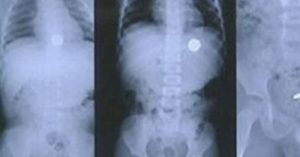

- Рентген. Позволяет обнаружить местонахождение монеты;

В отличие от пластмассовых деталей монету легко отследить на рентгене.

Желудок

Если рентген показал, что монета, которую проглотил малыш, покинула пищевод, избирается выжидательная тактика. Врачи дают ребенку от 2 до 5 дней на то, чтобы инородное тело вышло самостоятельно. В стационар малыша не кладут, однако предупреждают, что при появлении болей в животе необходимо немедленно обратиться в больницу.

Примерно в 30% случаев монета не выходит за отведенное время. Тогда следует повторно обратиться в больницу и сделать еще один снимок. Врачи сравнят этот снимок с предыдущим и посмотрят динамику.

- На следующий день делают рентген. Если выясняется, что монета находится в желудке и движение отсутствует, то принимается решение о проведении ФГДС (гастроскопии) для удаления инородного тела.